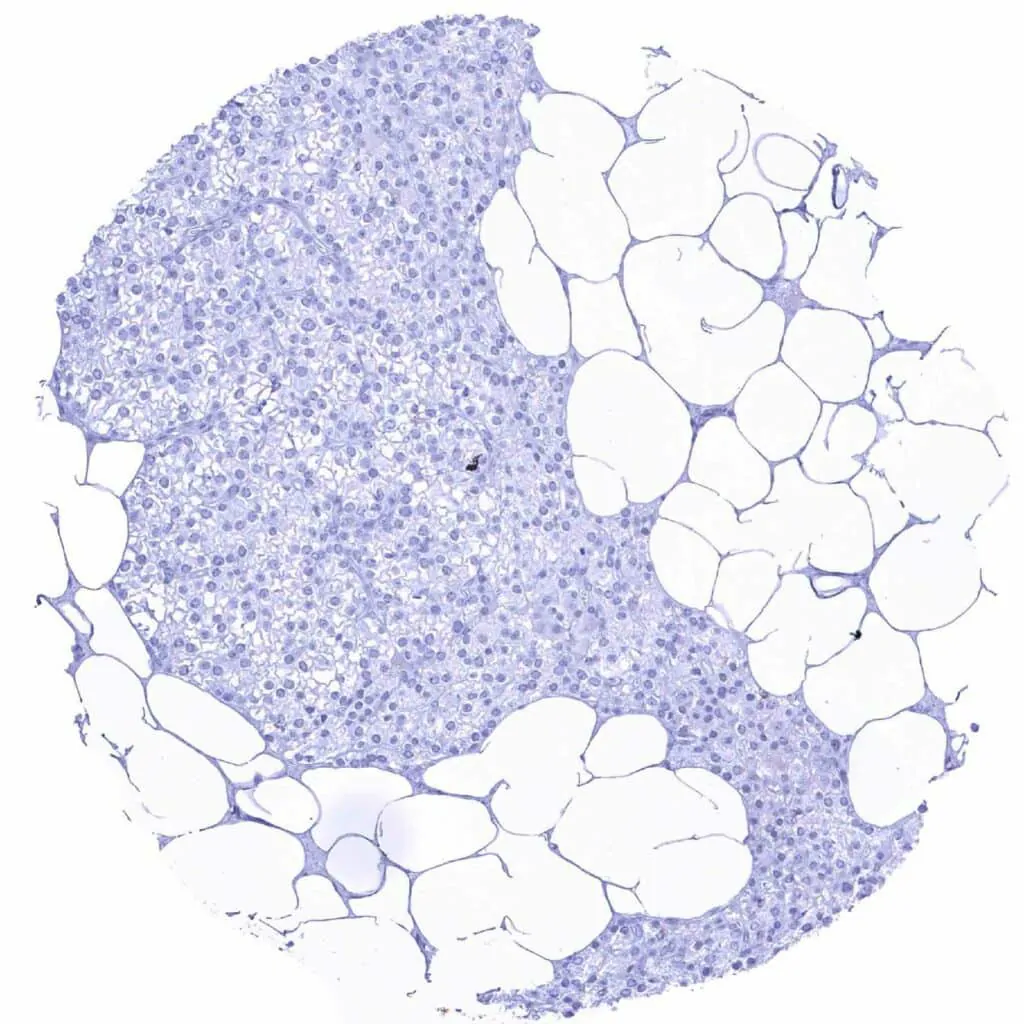

Bone marrow – Distinct CD38 staining of a subset of cells